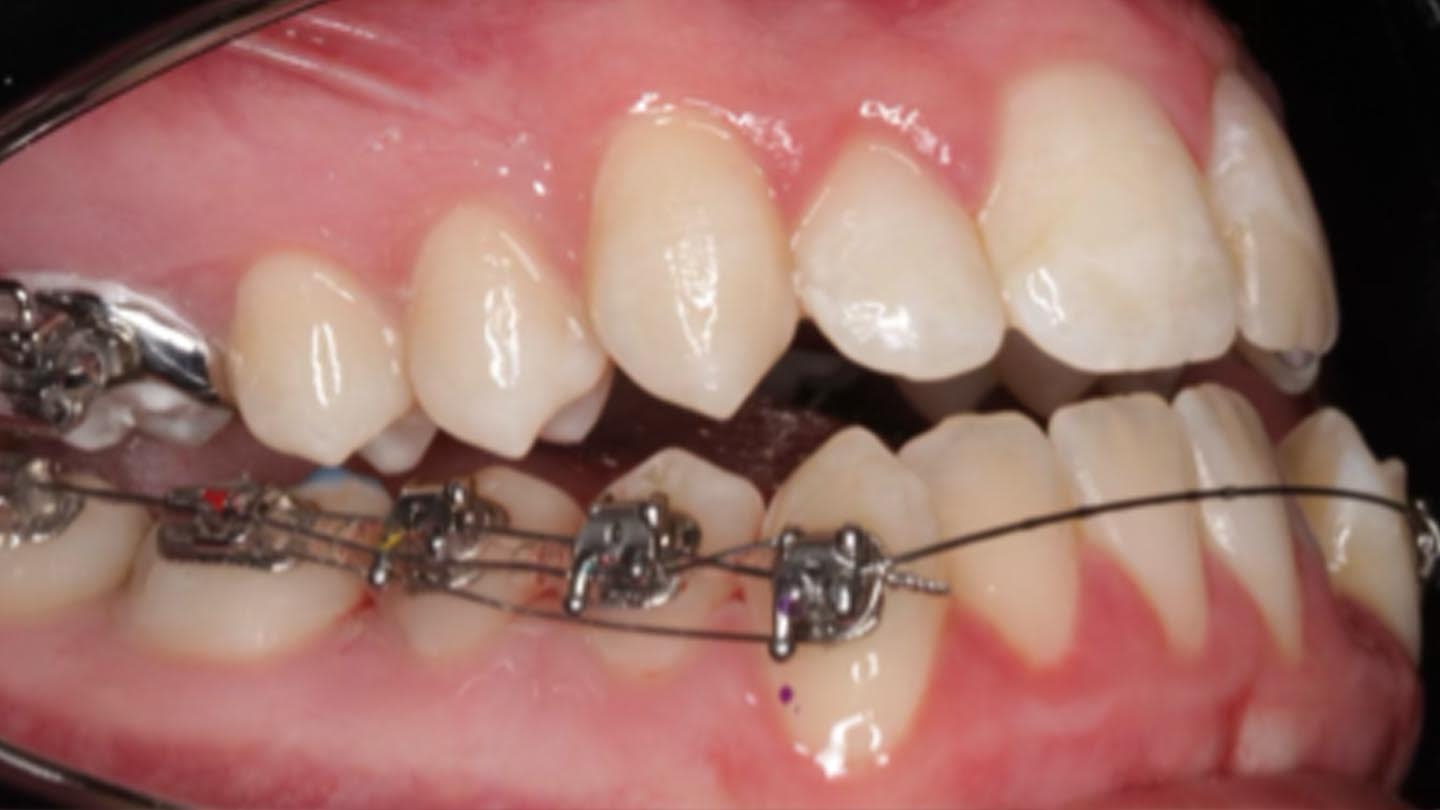

Despite variability in appliance design, all studies reported favorable outcomes with skeletal expanders for addressing transverse deficiencies in young adults. A case presentation illustrating treatment in a 16-year-old patient is shown in Figure 2 through Figure 39. (An additional case presentation may be viewed at compendiumlive.com/go/cced2110.) The studies also agree on the importance of individualizing miniscrew length and diameter in each case.25,26,30-32,34